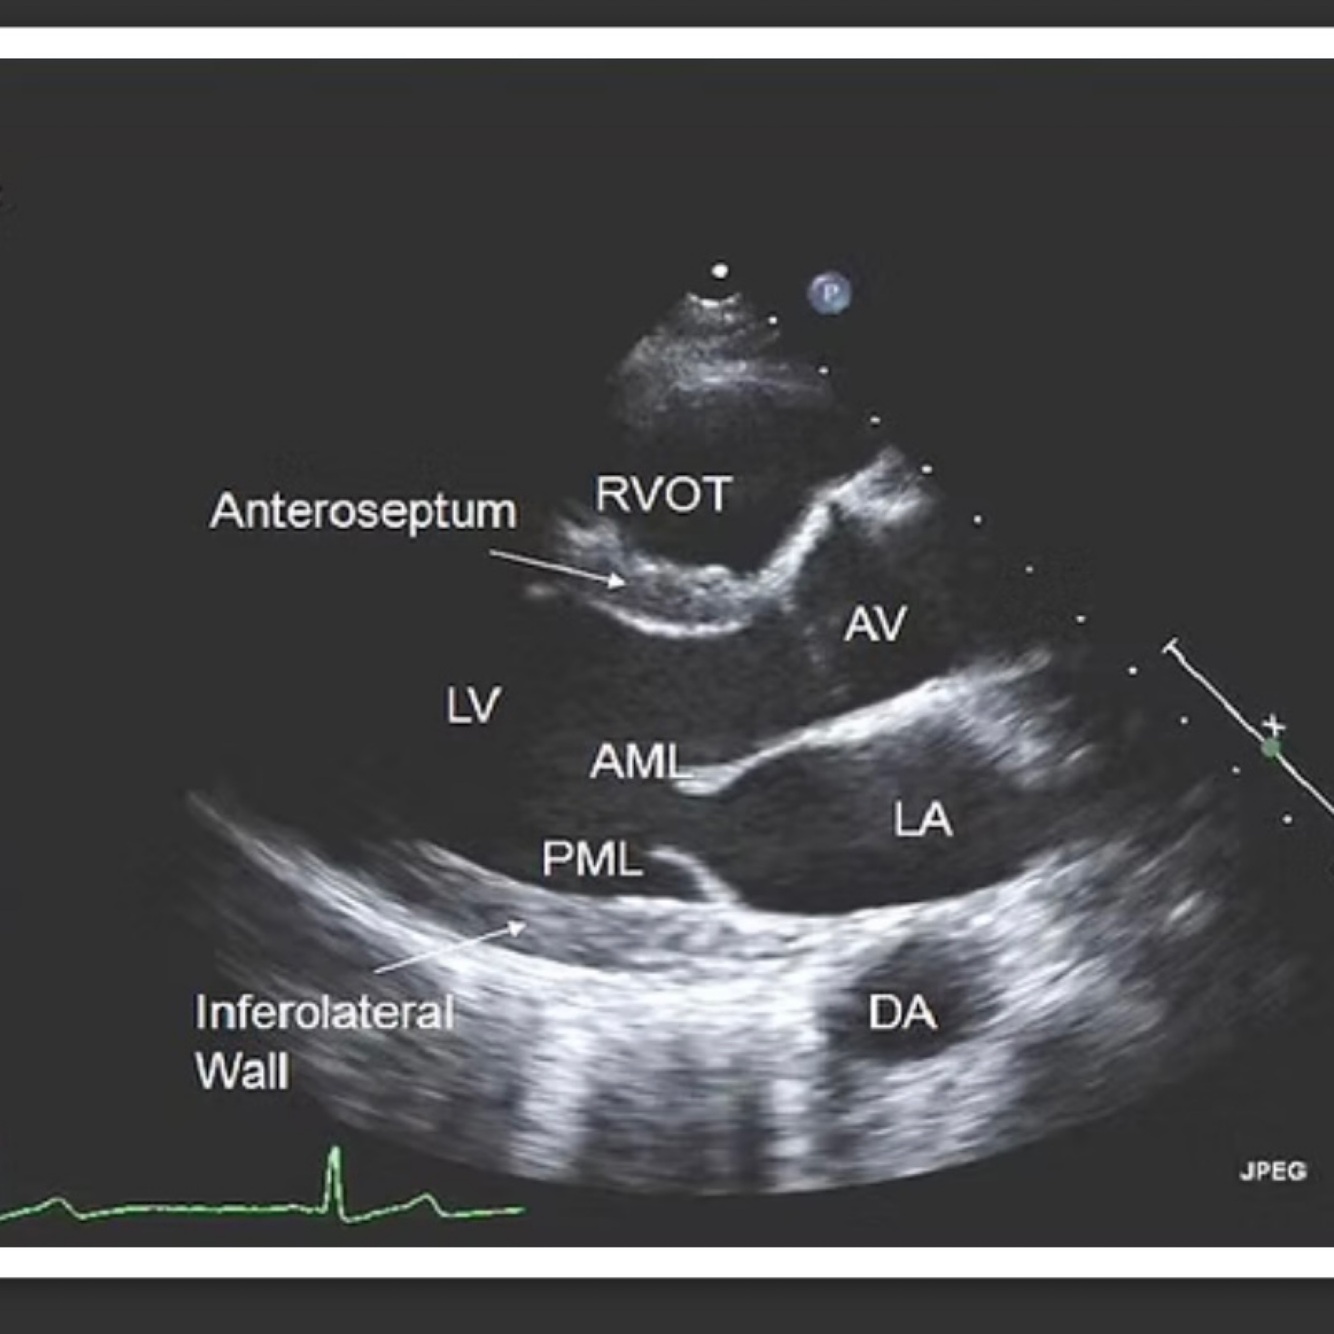

PLAX

Septum and posterior wall in true end diastole

LVOT in mid systole

Pathologies: MV prolapse, MR jet direction, MR vena contracta, AR vena contracta, pericardial effusion, pleural effusion